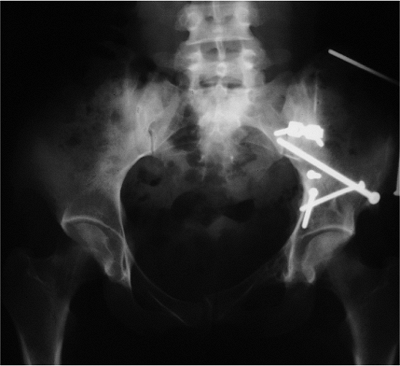

accident, sustaining an associated both-column fracture of the

acetabulum. AP pelvis and 45-degree oblique radiographs are shown in Figure 42.31.

The patient underwent open reduction and internal fixation (ORIF) of

her fracture through the ilioinguinal approach. An AP radiograph at the

4-year follow-up showed that the fracture healed with maintenance of

the hip joint (Fig. 42.32). Her hip function was normal.

![]() |

Figure 42.31. A. AP pelvis, (B) obturator oblique, and (C) iliac oblique radiographs of an associated both-column acetabulum fracture.

|

Figure 42.32.

AP pelvis radiograph at 4-year follow-up. The fracture is healed, and the hip joint is rated excellent based on both radiographic and clinic examination. |